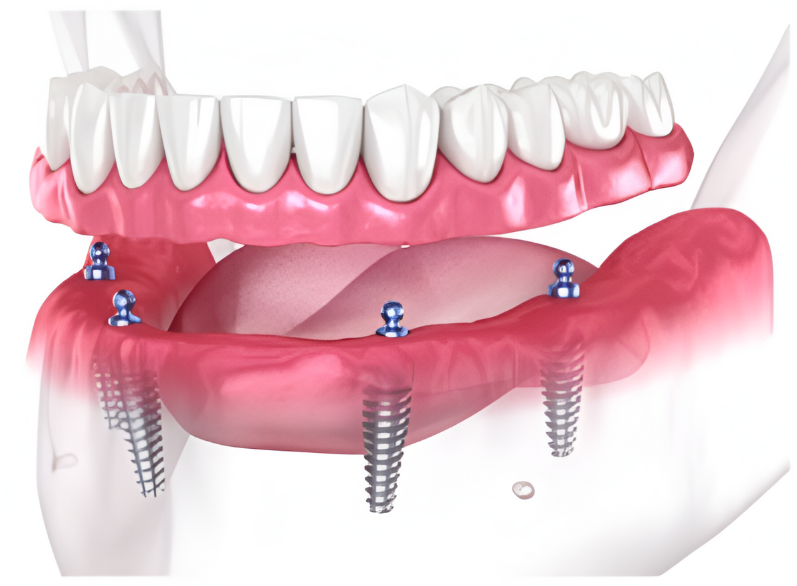

Includes everything from start to finish. No hidden fees.

Includes surgical placement of 2 to 4 implants.

Includes abutments

Includes healing denture.

Includes final snap-on implant denture.

Patients no longer have to deal with low-quality temporary solutions like dentures, bridges, or partials. Dental implants are the new leading standard in tooth replacement options. They act and feel just like real teeth with an average lifespan of 20+ years.

So, how do they work?

Every single dental implant consists of three parts - the implant, the abutment, & the crown. The implant is made of medical grade titanium. This part is surgically placed into the patient’s jaw bone and left to heal for 4-6 months afterwards.

This implant piece acts as the foundation for the rest of the tooth. Once the bone around the site has healed, the abutment and crown are placed on top of the implant. The end result is a beautiful, natural-looking new tooth!